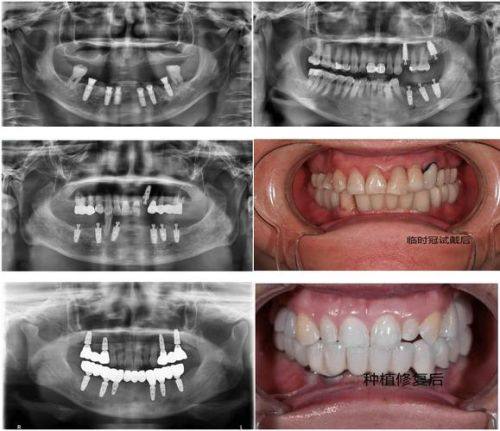

5. 全口咬合重建(种植):对于一些牙齿重度缺失或咬合功能紊乱的患者,全口咬合重建(种植)是一种有效的治疗方法。何医生能够综合考虑患者的口腔情况、咬合关系和全身健康状况,制定个性化的治疗方案。通过种植牙齿和修复,修复患者的咬合功能和咀嚼能力,提高患者的生活质量。

1. 老先生实例:有一位老先生,牙齿缺失多年,面容憔悴,生活质量重度下降。由于牙齿缺失,他吃饭只能吃一些软烂的食物,特别多美食都无法享受,整个人也变得越来越没有自信。他来到何思铃医生这里后,何医生为他进行了详细的检查和评估,制定了全口种植牙的方案,并采用了全新的数字化种植技术。在手术过程中,何医生操作精细,尽量减少了老先生的痛苦。术后,老先生的牙齿修复得非常好,他又能像以前一样品尝各种美食了,面容也变得更加精神,重新找回了自信。老先生对何医生的医术和服务赞不绝口,他说:“何医生不仅技术好,而且态度特别亲切,让我特别安心。现在我的牙齿好了,生活都变得更有滋味了。”